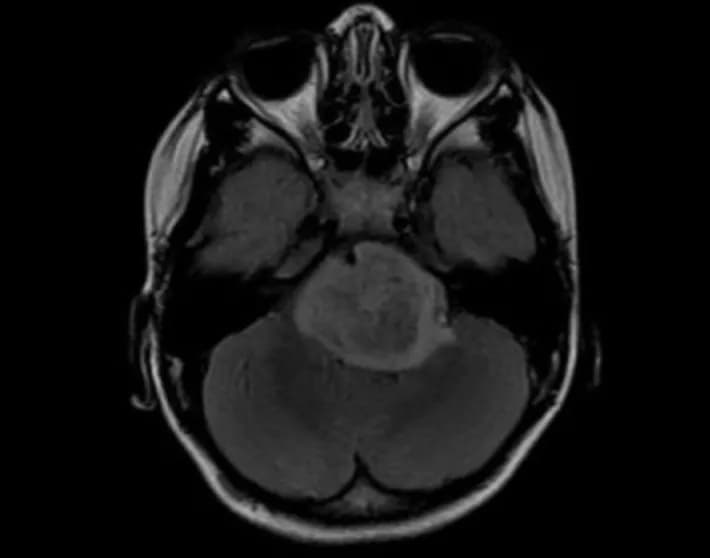

High-grade gliomas are a group of deadly brain tumors that include adult glioblastoma, the brain cancer now affecting U.S. Sen. John McCain of Arizona; anaplastic oligodendroglioma; pediatric glioblastoma; and a pediatric tumor called diffuse intrinsic pontine glioma. Five-year survival rates are 60 percent for anaplastic oligodendroglioma, around 10 percent for adult and pediatric glioblastomas and virtually nonexistent for DIPG. New treatments are urgently needed.

In the new study, Monje's team examined mice that were genetically engineered to lack neuroligin-3. These mice have nearly normal brain function. However, when their brains were implanted with any of the forms of human high-grade glioma, the cancer cells could not proliferate. The growth stagnation persisted for several months.